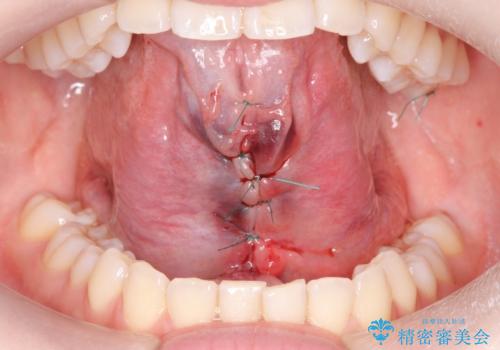

- ら行が言いにくいとの事で来院。舌の動きを舌小帯が邪魔していたので舌小帯の形成術を行いました。

舌小帯の形成手術を行うことにより舌が口蓋に届くようになり

ら行が言いやすくなりました。

舌小帯の手術は当日行うことができます。